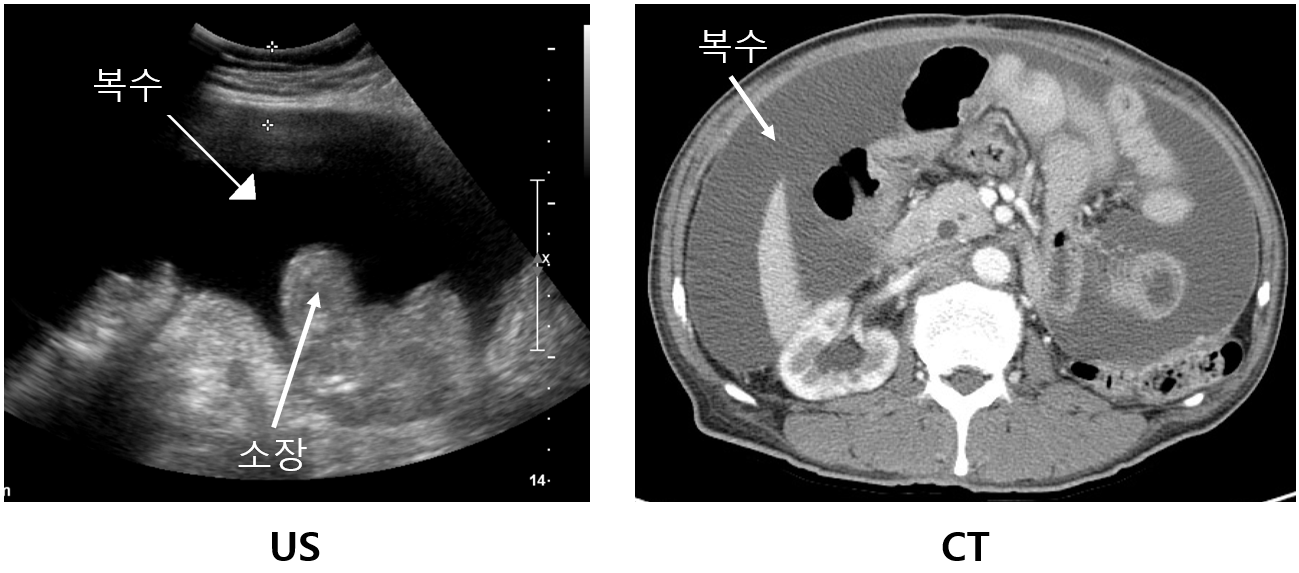

(1) US: 복강 내 hypoechoic fluid

(2) CT: 복강 내 hypoattenuating fluid